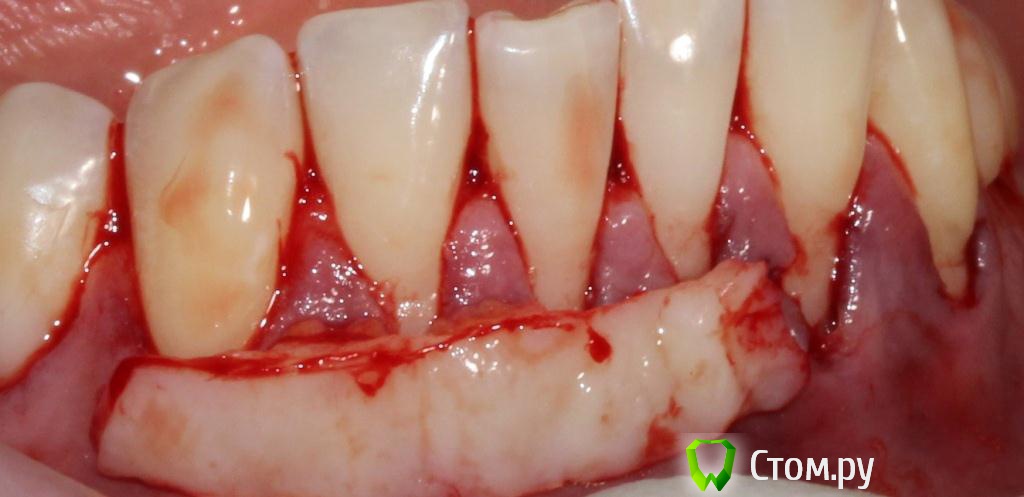

Популярный пост zzkz Опубликовано 18 сентября, 2014 Популярный пост Поделиться Опубликовано 18 сентября, 2014 (изменено) Жалобы эстетические и сильная чувствительность Рецессия от 34 до 44 Подготовка поверхности корней только скэйлинг СДТ с 2-х сторонНа небе каппа Ушивание пролен 6-0 2 недели после Чувствительности нет на сегондя. Ждать ли еще убыли или прироста? Сосочек закрыл "черный треугольник". Не уйдет ли? Изменено 18 сентября, 2014 пользователем zzkz 33 Ссылка на комментарий

zzkz Опубликовано 18 сентября, 2014 Автор Поделиться Опубликовано 18 сентября, 2014 (изменено) Корни обрабатывали чем нибудь?Только механически кюретами, доксициклин не использовал. Решил так попробовать, увидел тут на форуме у кого-то. Сильно критично? Изменено 18 сентября, 2014 пользователем zzkz Ссылка на комментарий

zzkz Опубликовано 19 сентября, 2014 Автор Поделиться Опубликовано 19 сентября, 2014 Чем тонель формировали?с оптикой работа? купил такой инструмент. Дерь...мо если честно)) И что то мне подсказывает он для чего то другого предназначен) Жду выставки в Москве, надеюсь что нибудь найду. У какой торгующей фирмы можно посмотреть инструменты кто подскажет? Работа в бино *3,0. Делал около 2,5 часов Скоростуха не та. Это моя первая работа такого рода 2 Ссылка на комментарий